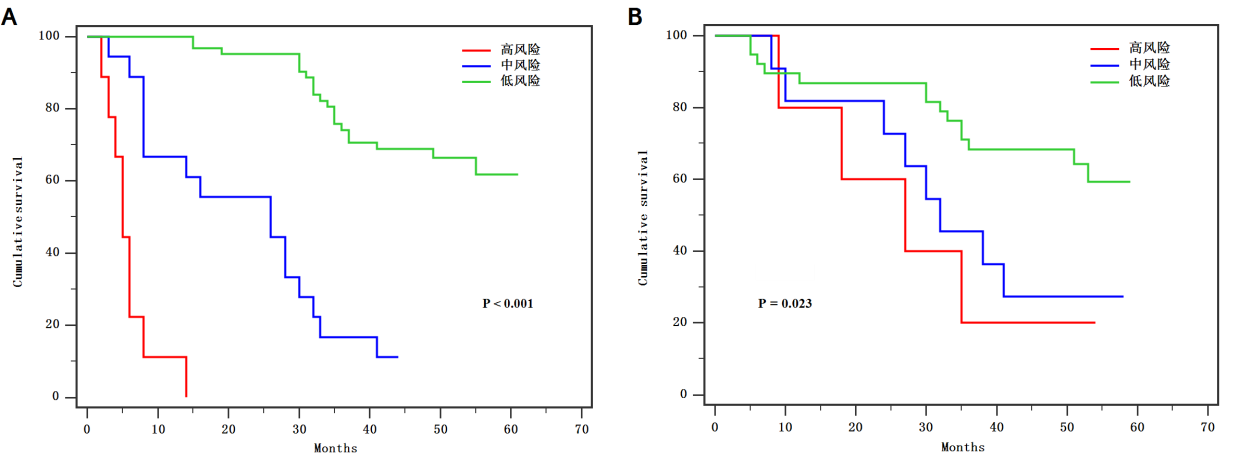

基于MDCT影像组学特征的模型对于预测胃癌淋巴结转移具有较高的准确度��,可为胃癌的个体化诊治提供基础信息����,有助于提高对临床决策的信心����。此外���,基于影像组学的模型还具有对胃癌患者预后分层的潜力���。

图8 (A)训练队列和(B)验证队列依据诺模图分层的胃癌患者的总体生存曲线